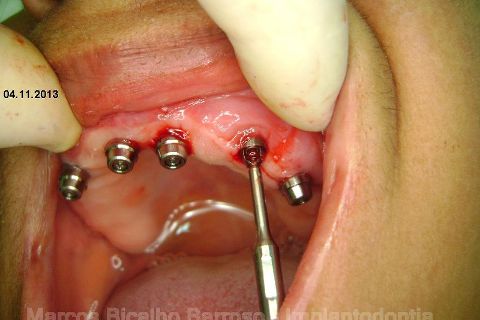

Atualização do caso clínico que já postei, "REABILITAÇÃO EM MAXILA ATRÓFICA COM IMPLANTES", um caso que inclui expansão do rebordo estreito com cinzel e martelo, expansores rosqueáveis, enxerto e instalação dos implantes distais inclinados tangenciando seio maxilar. Inclui esvaziamento do forame nasopalatino e preenchimento com biomaterial para instalação de dois implantes próximos dele. Cirurgia realizada em única sessão, com instalação dos 6 implantes. Para os colegas que não conheceram e/ou esqueceram da apresentação, este é o resumo do caso na fase cirúrgica.http://www.youtube.com/watch?v=BtvexFexRPA&hd=1

FASE PROTÉTICA DA REABILITAÇÃO EM MAXILA ATRÓFICA...incluindo a reabertura, instalação dos minipilares e PTR provisória reembasada sobre os cilindros de proteção.